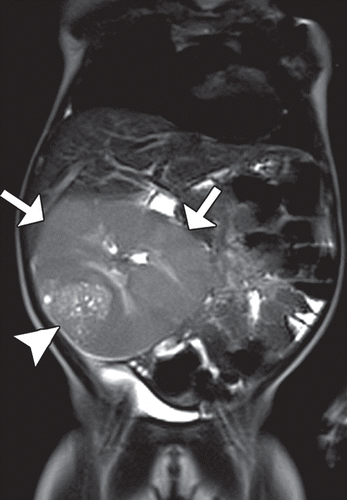

Nephroblastomatosis

Picture of nephroblstomatosis + Wilms

Screening ultrasound every 3 months until patient turn 8